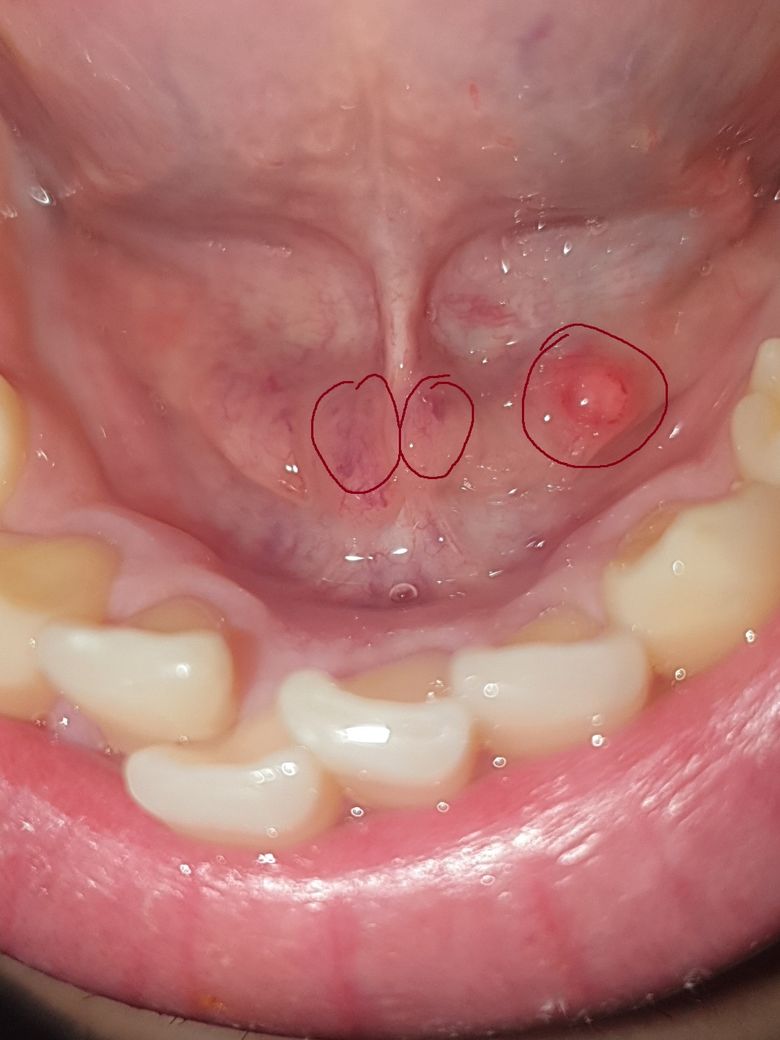

혀 밑에 물집 ? 이 생겼는데 괜찮은 걸까요 ?

혀를 움직일 때 이전과는 다른 이질감이 들어 거울을 보고 확인했더니

혀 밑에(동그라미 친 부분) 물집 같은 게 생겼더군요 ...

• 2번 째 사진

나란히 2개 붙은 동그라미 부분은 정상적으로 침이 나오는 구멍으로 보입니다. 뒷쪽 큰동그라미 부위는 물집이 잡힌 것으로 보이며 주로 상처 때문에 생기는 점액성 수포로 보입니다. 사이즈가 작아 저절로 없어질 가능성이 높아 보입니다. 3-4일 정도 기다려 보시고 저절로 안 없어지면 치과에 가서 흐트리면 됩니다.

점액종으로 보입니다. 점액종이란 점막내부에 조직액이 차게 됨으로써 생기게 되는데 .물집과 비슷해요. 보통 마찰력이 많이 가해지거나 .외부 자극이 되었을 경우에 생기는 경우가 많습니다.

치과병원에서 간단하게. 제거할수 있습니다. 자세한 확인을 위해서 치과병원에서 진료를 받아보세요.